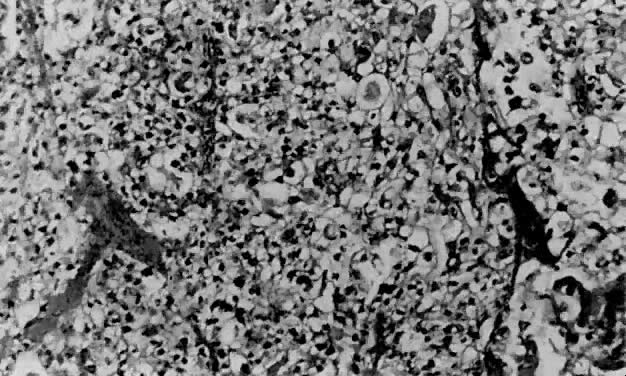

Serous carcinoma is a relatively uncommon type of endometrial carcinoma, accounting for about 5% to 10% of cases. This is an especially aggressive variant, with patients often presenting with stage II or III disease, deep myometrial invasion (40% to 50%), and frequent vascular invasion.21 The mean patient age is 70 years,45 somewhat older than for patients with endometrioid carcinoma. It occurs disproportionately in African-American women. Whereas about 53% of patients with endometrioid carcinoma have a history of exogenous estrogen use, only 21% of patients with serous carcinoma have such an association.21 Nulliparity is not a common epidemiologic factor in serous carcinoma. These tumors have a predilection for peritoneal spread, similar to primary ovarian serous adenocarcinoma.24 A papillary configuration is frequently present histologically (Fig. 10), but these lesions may grow in a solid or acinar pattern. For this reason, this variant should be referred to as serous carcinoma rather than papillary serous carcinoma. Papillae, when present, have fibrovascular cores that are lined by pleomorphic, hyperchromatic nuclei with eosinophilic macronucleoli (nuclear grade 3). Not infrequently, large, bizarre nuclei, often multinucleated, are observed. Cellular stratification and tufting or budding are frequently found (Fig. 11). The surface of the papillae are irregular and jagged, unlike the smooth surface of the villoglandular variant of endometrioid carcinoma. The solid or acinar patterns show cellular features as described above. Psammoma bodies (Fig. 12) are seen in about a third of cases. Due to the usually high nuclear grade, advanced stage of disease, deep myometrial invasion, and vascular space invasion, patients tend to have a poor prognosis, with a 25% to 35% 5-year survival rate45,46,47 and a 14% 10-year survival rate.47 Lung and liver are the most common sites of metastasis48 in advanced-stage serous carcinoma of the endometrium.

Fig. 10. Complex arborization of papillary structures is seen in serous carcinoma. Cellular budding and tufting can often be appreciated under low power.

Fig. 11. Serous carcinoma. The papillae have fibrovascular cores and are lined by vesicular nuclei with prominent eosinophilic nucleoli. Small clusters of cells that have separated from the papillae are referred to as cellular budding ( arrow ).

Fig. 12. Although more commonly seen in serous carcinoma, psammoma bodies ( arrow) may also be found in the villoglandular variant of endometrial carcinoma.